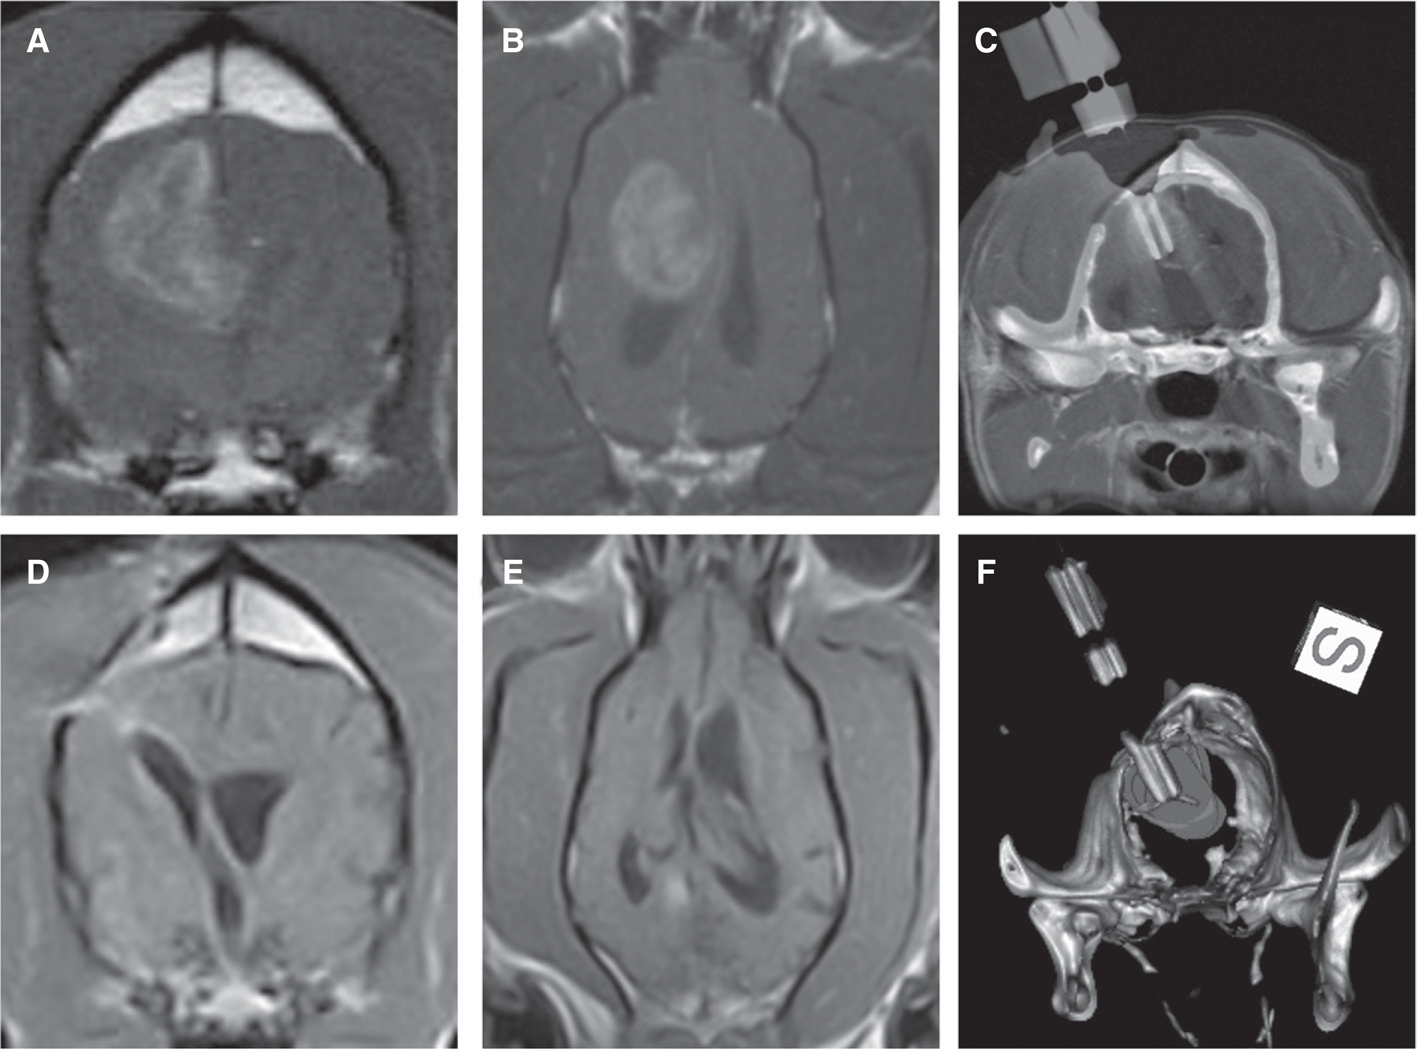

Canine subjects enrolled in the trial have mild-to-moderate clinical signs of brain dysfunction and histopathologically confirmed gliomas demonstrating immunoreactivity to IL-13RA2 and/or EphA2. The trial is designed using a 3+3 dose-escalation scheme, with cohorts administered 0.05, 0.1, 0.2, or 0.4 μg of each cytotoxin/ml of infusate. To optimize the CED procedure, an inverse therapeutic planning method, using a spherical shape–fitting algorithm generated from patient-specific, segmented MRI/CT images, is used to simulate ideal cannula placement and target coverage prior to treatment (69, 70). CED is performed in the anesthetized dog using reflux-preventing cannulae to co-administer the cytotoxins with a gadolinium tracer (Figure 2) to allow for intraoperative MRI visualization of infusate distribution. Tolerability is defined as the absence of dose-limiting toxicities (DLT) within 28 days of infusion. DLT are considered the development of Grades 3, 4, or 5 adverse events, as defined by the Cancer Therapy Evaluation Program CTCAE standards (71). Serial clinical, laboratory, and brain MRI examinations are performed for 6 months following CED treatment, and the CED infusions can be repeated in the event of tumor progression or suboptimal target coverage is achieved during the initial infusion. Efficacy is determined by characterizing objective tumor responses using RANO and volumetric criteria modified for use in canine patients (72).

Figure 2 Intratumoral convection-enhanced delivery (CED) of molecularly targeted therapeutics into a canine astrocytoma. Pre-treatment transverse T2-weighted (A) and post-contrast T1-weighted (B) images demonstrating the tumor in the temporal-piriform lobes of the brain. (C) Fused silica and ceramic reflux-preventing cannula (RPC) with multistep tip design used for CED. (D) Intraoperative, transverse T1-weighted images obtained immediate prior to infusion, showing probe guide pedestal (PGP) implanted in the skull, through which RPC (F, white arrow) will be stereotactically placed into the tumor. (E–J) Time-lapsed 3DT1-weighted images taken over approximately 2 h of MR-monitored infusion showing progressively increasing volume of distribution of the infusate co-delivered with gadolinium (white) within the tumor. An additional RPC has been inserted (G, red arrow) to facilitate tumor coverage. (K) Immediate post-infusion T1-weighted image demonstrating tumor coverage and infusate containment achieved at completion of CED.

Using this approach, we have achieved robust and clinically relevant volumes of infusate distribution in unresected canine MGs (Figure 2). In addition, inclusion of real-time MR-monitoring-facilitated intraoperative cannulae revisions that allowed continued target coverage after observation of ventricular leakage or infusate reflux in some procedures. Clinical and partial tumor volumetric responses (≥50% volumetric tumor reductions) have been observed in 55% (5/9) of the dogs treated to date. Necropsy examinations performed in four dogs with progressive disease have revealed tumor necrosis in infused regions. In the first three dosing cohorts, significant DLT have not been observed. Results from this trial indicate that improvements in CED cannula design, therapeutic planning, and MRI monitoring allow for safe and effective intratumoral delivery of IL-13RA2- and EphA2-targeted cytotoxins. This ongoing study also provides preliminary evidence of the efficacy of these cytotoxins when used as a monotherapy in a spontaneous animal glioma model.